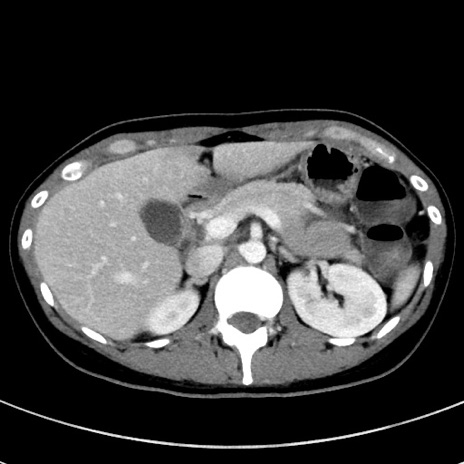

症例17(横断像)

【症例】20歳代女性

【主訴】嘔吐、下腹部痛

【現病歴】昨日夕食後に嘔吐し下腹部痛が出現。本日になっても嘔吐持続し改善しないため来院。

【身体所見】意識清明、BT 37.2℃、BP 108/67mmHg、腹部:平坦、やや硬、下腹部正中から右にかけて圧痛あり、反跳痛軽度あり、tapping pain(+)。

【データ】WBC 13600、CRP 14.94